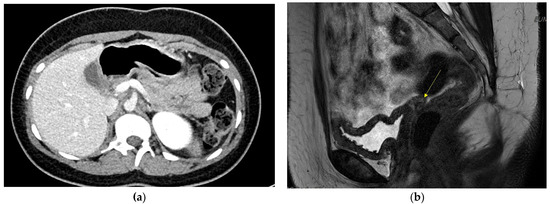

On admission, the random blood glucose level was 464 mg/dL, and HbA1c was 19.9%, without ketoacidosis. Fasting serum insulin was 3.2 uIU/mL (normal reference: 2.5–25 uIU/mL) and c-peptide was 1.4 ng/mL (reference: 1.1–4.4 ng/mL). Pancreatic autoantibodies (glutamic acid decarboxylase and insulin antibody) were negative. Abdominal computed tomography (CT) revealed dorsal pancreatic agenesis, uterine agenesis, rotation anomaly of the right kidney, chronic left portal vein thrombosis with left lobe hypotrophy of the liver, and scoliosis. Figure 1a shows dorsal pancreatic agenesis in the abdominal CT scan. Karyotype analysis was performed to rule out Turner syndrome, considering the patient’s short stature and primary amenorrhea. The results revealed 46,XX. Chromosomal microarray analysis was performed using the SNP array method (CytoScan Dx Assays, Genome build: hg19). A 1.5–Mb heterozygous deletion at 17q12 (arr[hg19] 17q12 (34,822,465–36,283,612)x1) was identified. This led to the diagnosis of chromosome 17q12 deletion syndrome. The main OMIM genes involved were HNF1B, LHX1, ZNHIT3, PIGW, AATF, TADA2A, DUSP14, DDX52, ACACA, SYNRG, and GGNBP2. The patient manifested diabetes mellitus, uterine agenesis, and developmental delay, consistent with the genetic diagnosis.

Figure 1. (a) Dorsal pancreas agenesis in Abdomen CT.; (b) Absent uterus and upper vagina in pelvis MRI. Yellow arrow shows absent uterus.

Gynecological examination was performed by a gynecologist. On physical examination, a micro-perforate hymen and underdeveloped clitoris were noted. Pelvic magnetic resonance imaging (MRI) revealed an absent uterus and upper vagina. Figure 1b shows the patient’s pelvic MRI. Bilateral uterine buds and triangular soft tissue in the pelvic cavity were noted, suggesting Müllerian remnants. The patient was diagnosed with MRKH syndrome. Both ovaries with follicles were also noted. The results of the hormone tests indicated luteinizing hormone of 3.5 mIU/mL, (reference range: 0.4–11.7 mIU/mL), follicle-stimulating hormone of 4.2 mIU/mL, (reference: 1.0–9.2 mIU/mL), and estradiol of 39 pg/mL (reference: 34–170 pg/mL). Surgery or vaginal dilatation therapy will be required when the patient reaches adulthood.